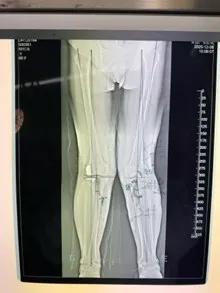

經(jīng)過(guò)詳細(xì)的體格檢查、影像學(xué)評(píng)估和三維重建,醫(yī)療團(tuán)隊(duì)確認(rèn)鮑奶奶的情況非常適合進(jìn)行膝外側(cè)單髁置換術(shù)。這種微創(chuàng)手術(shù)創(chuàng)傷小、恢復(fù)快,能夠最大程度保留膝關(guān)節(jié)的自然結(jié)構(gòu)和功能。

手術(shù)當(dāng)天,骨科團(tuán)隊(duì)采用微創(chuàng)切口,僅約8厘米,遠(yuǎn)小于傳統(tǒng)全膝關(guān)節(jié)置換手術(shù)切口。術(shù)中精準(zhǔn)定位,僅置換病變的膝關(guān)節(jié)外側(cè)間室。

手術(shù)使用了最新的單髁假體系統(tǒng),這種假體設(shè)計(jì)更符合人體工程學(xué),能夠更好地恢復(fù)膝關(guān)節(jié)的自然運(yùn)動(dòng)軌跡。